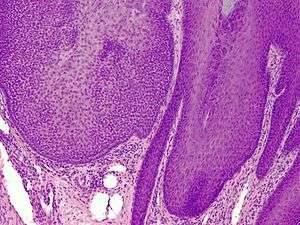

A trichilemmoma on a forehead.

Trichilemmoma (also known as "tricholemmoma"[1]) is a benign cutaneous neoplasm that shows differentiation toward cells of the outer root sheath.[2]:673[3] The lesion is often seen in the face and neck region. Multifocal occurrence is associated with Cowden syndrome, in which hamartomatous intestinal polyposis is seen in conjunction with multiple tricholemmoma lesions.